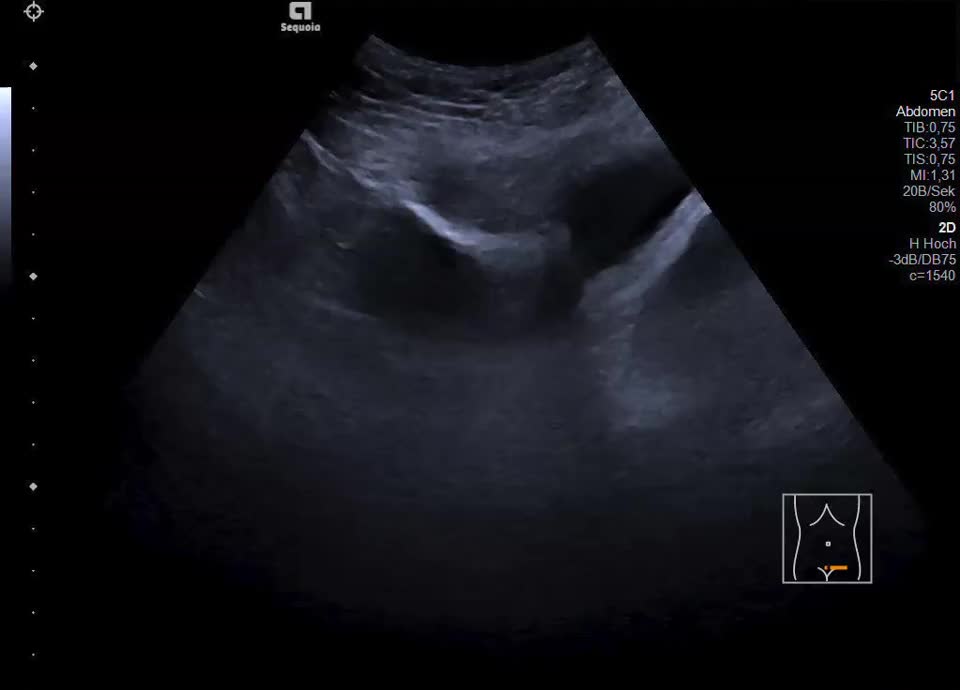

Zystisch-solide Lebermetastase bei Ovarialkarzinom

Es zeigt sich subkapsulär in Segment VI der Leber eine zystische Raumforderung mit durchgehendem Kapselreflex und hyperechogenem solidem Anteil. Der Befund ist nicht vereinbar mit einer blanden Zyste, sondern suspekt auf eine zystisch-solide Metastase. In der ergänzenden CEUS nehmen die soliden Anteile in der arteriellen Phase Kontrastmittel auf und zeigen in den portalvenösen sowie späten Phasen eine persistierende KM-Anreicherung ohne Washout. Zusätzlich finden sich eine noduläre Peritonealverdickung im Oberbauch sowie ein zystischer Ovarialtumor mit soliden Anteilen im rechten Unterbauch. In Zusammenschau der Befunde besteht der dringende Verdacht auf ein hepatisch und peritoneal metastasierendes Ovarialkarzinom.